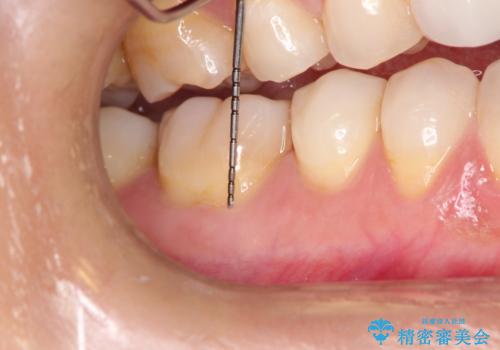

- 昔に受けた矯正治療がきっかけで歯肉が下がってしまった事を主訴として来院された患者様です。

結合組織移植術を行う方法を提案しましたが、傷口が口蓋にもできるのが嫌だとのことで、代替案としてバイオマテリアルを併用した根面被覆術を計画致しました。

治療対象部位は右下4,5,6番の3本です。

幸いなことに術後の痛みがほとんどなく、翌日には痛み止めも飲まずに済んだとのことでした。

治癒経過も良好で、患者様も満足されていました。また、知覚過敏も減ったとの事でした。